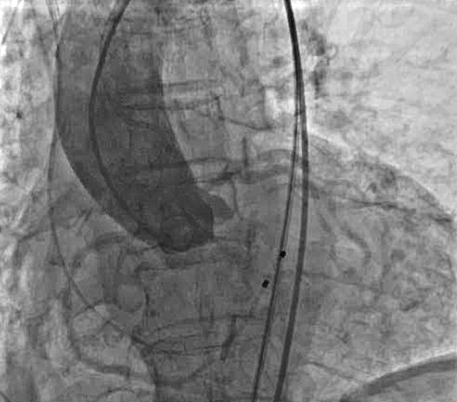

使用直头超滑导丝跨瓣后交换加硬导丝,行球囊扩张主动脉瓣,球囊扩张时行升主动脉造影,评估冠脉风险。

瓣膜定位及释放:将VenusA-Pro 23mm型号瓣膜系统送至主动脉瓣口处,以定位模式行造影,定位满意后释放瓣膜至工作位后,行定位造影,观察瓣膜位置及冠脉血流情况。瓣膜位置满意后完全释放瓣膜。